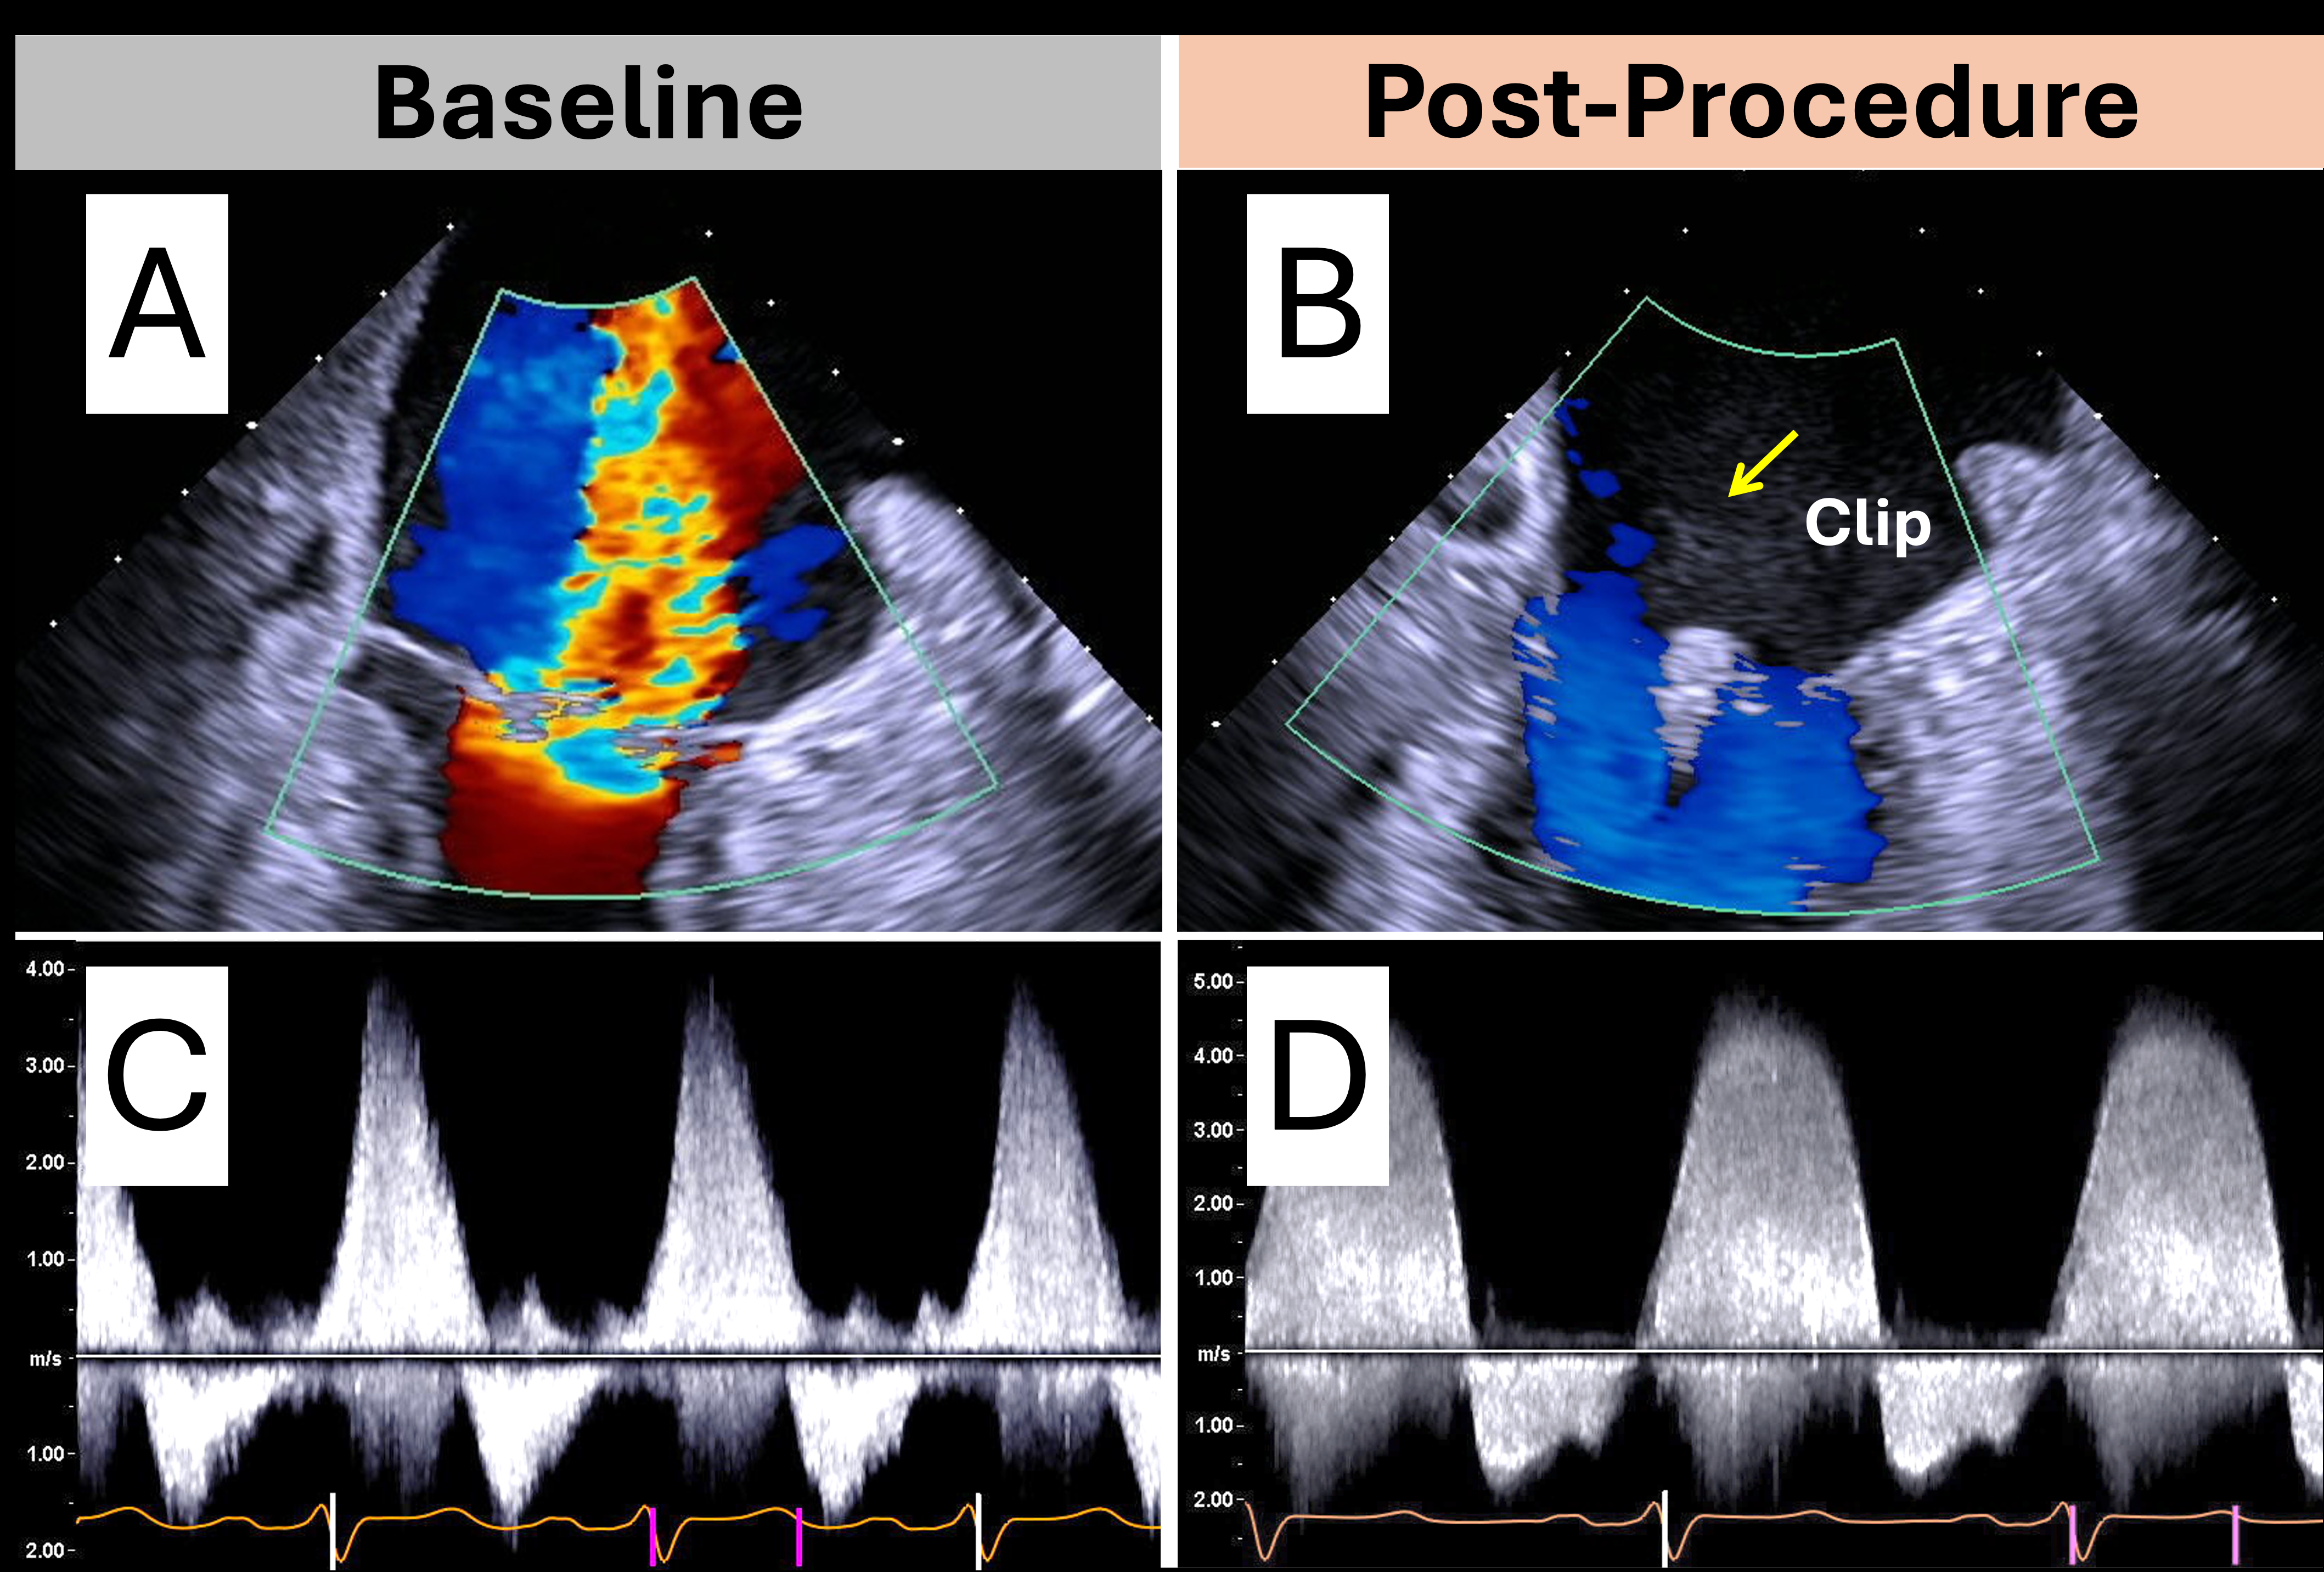

Case 1: An 80-year-old woman with severe degenerative MR had a large, central MR jet occupying most of the left atrium (LA) and an LVOT stroke volume of 31 mL. Post-TEER, the MR jet resolved and LVOT stroke volume rose to 53 mL.

Key echocardiographic indicators of resolved severe MR post-intervention include: (1) marked reduction in jet area on color Doppler, (2) increased LVOT stroke volume indicating improved forward flow, (3) transition from a dense, low-Vmax, triangular MR jet contour to a less dense, high Vmax, parabolic MR jet contour on spectral Doppler reflecting improved LA hemodynamics, (4) decreased transseptal pressure gradient across the iatrogenic ASD reflecting improved LA pressure, (5) shift from E-wave to A-wave dominant mitral inflow in the absence of significant mitral stenosis, (6) return of antegrade pulmonary S wave flow reflecting decreased LA pressure, and (7) reappearance of LAA SEC, as the MR jet no longer washes away the SEC seen in chronic atrial fibrillation. While no single measure is definitive, these findings support a multimodal approach to residual MR assessment and highlight the need for further validation.